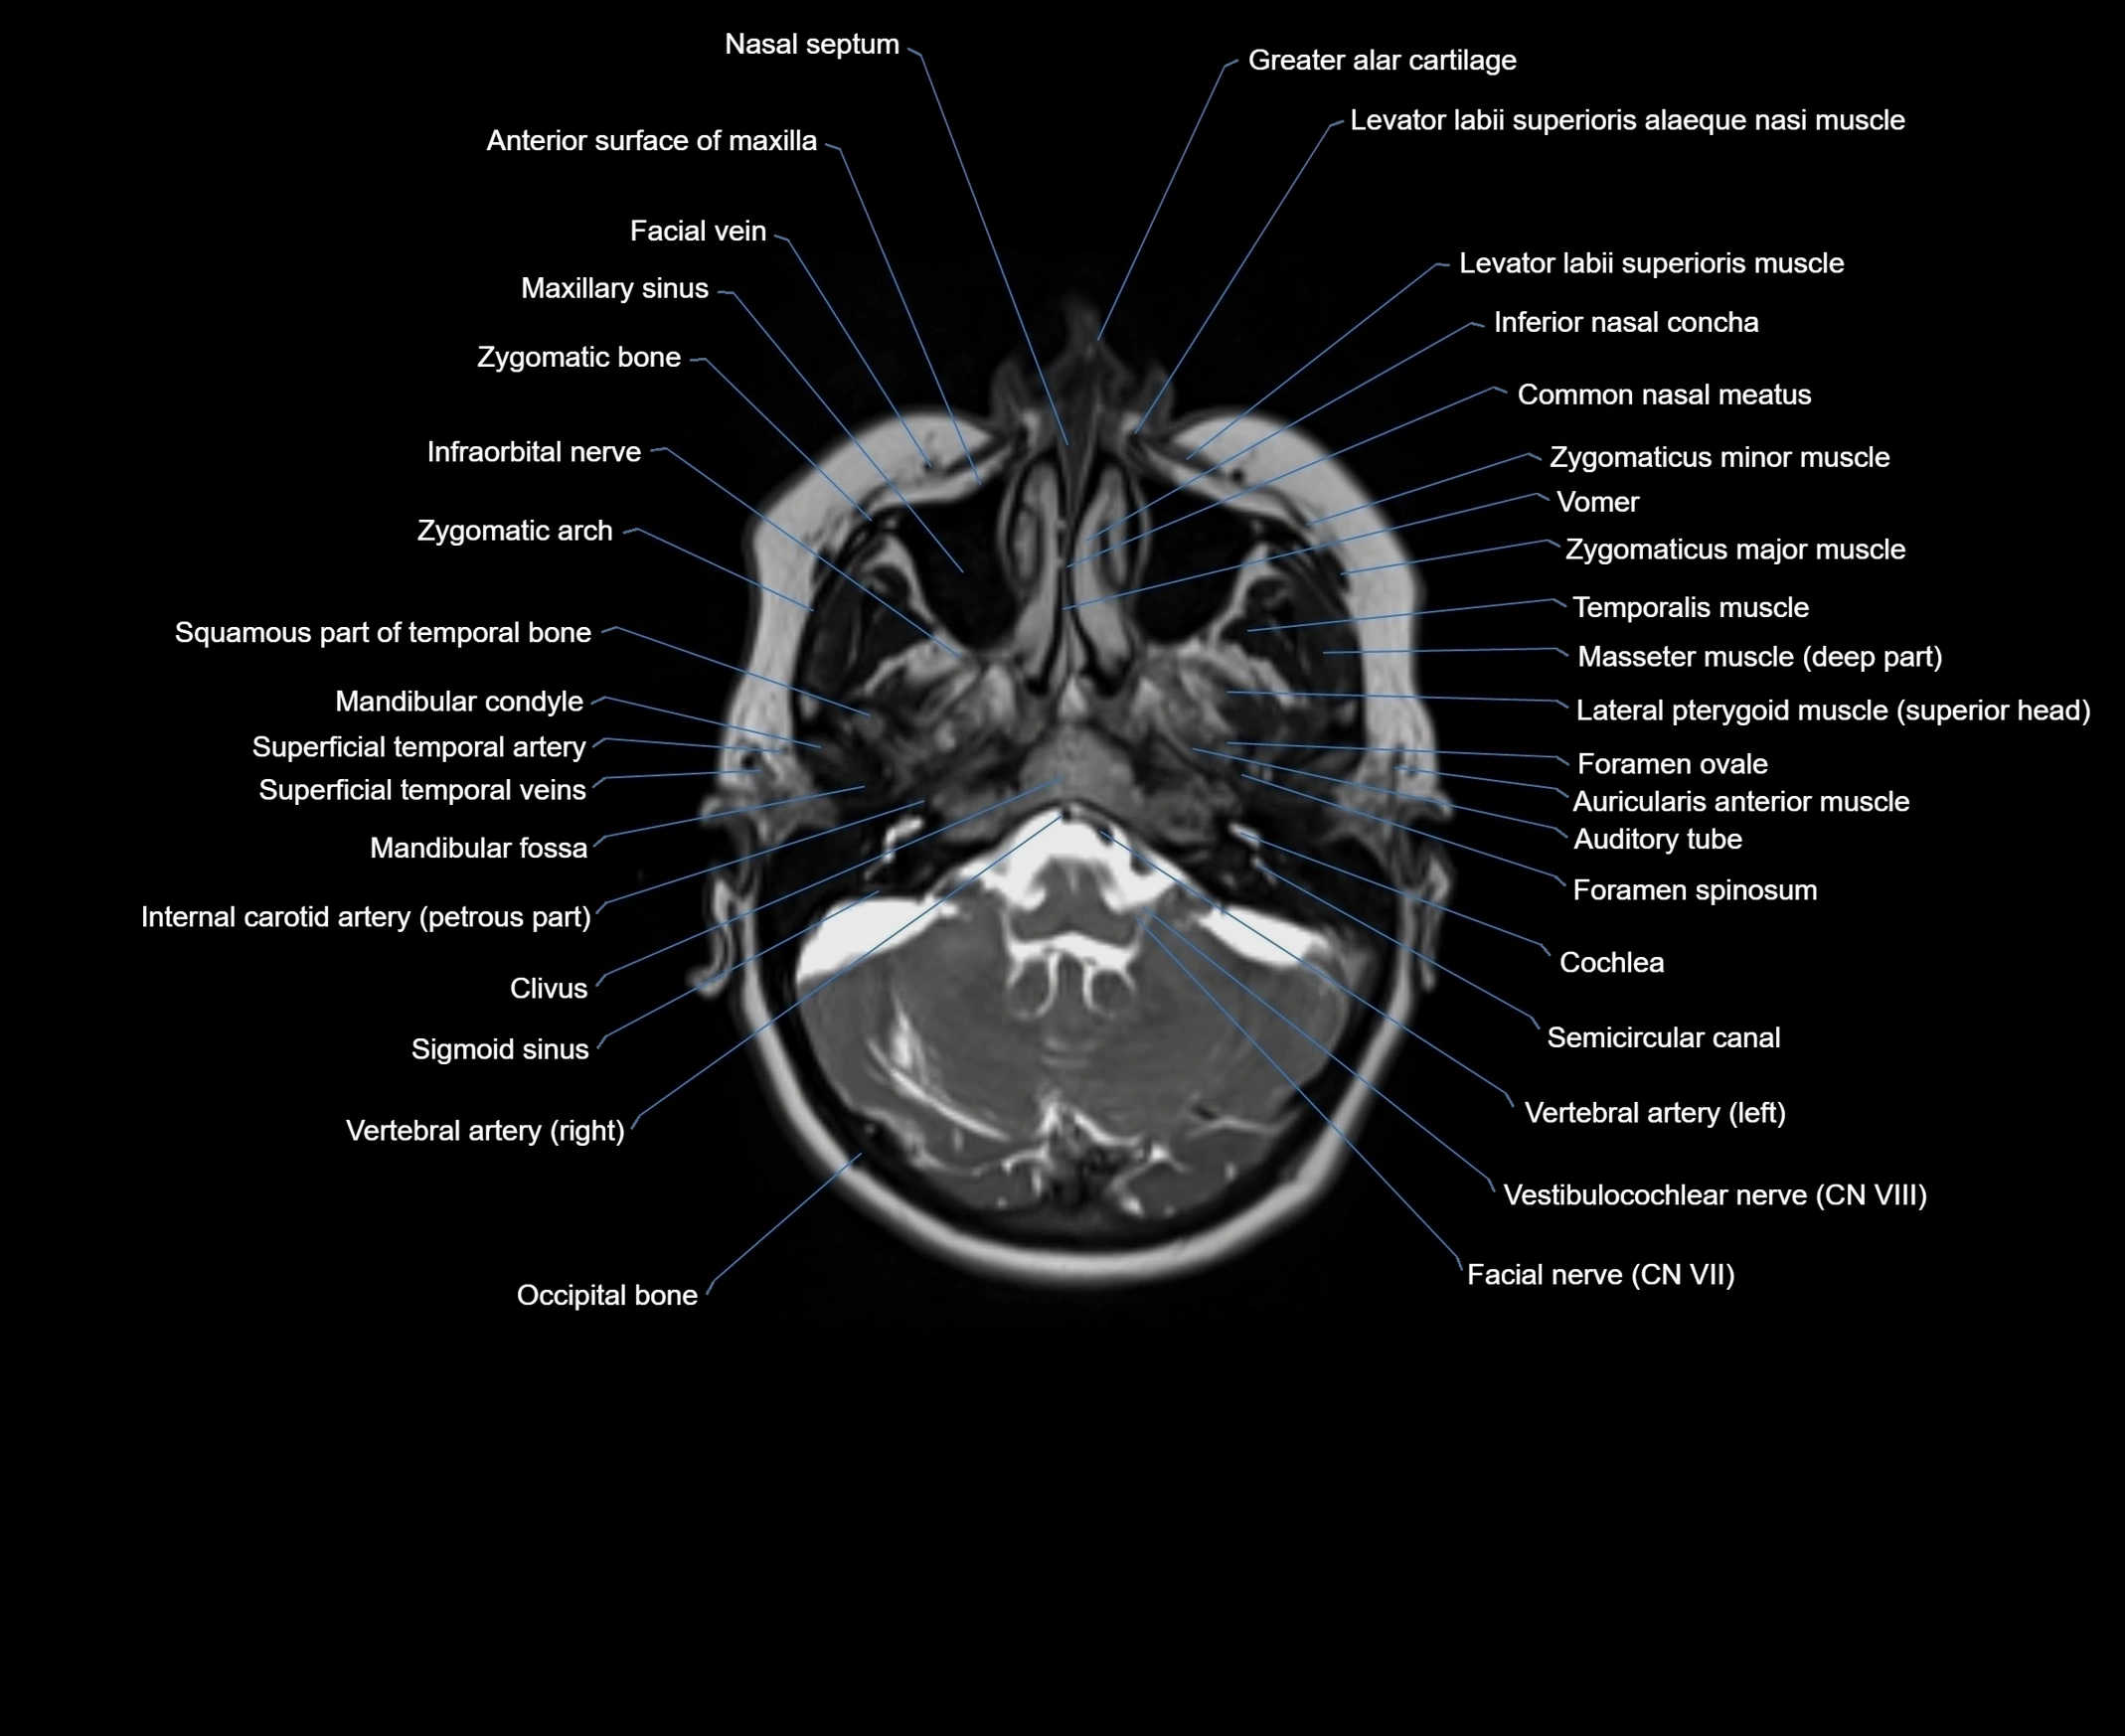

- Greater alar cartilage

- Levator labii superioris alaeque nasi muscle

- Levator labii superioris muscle

- Inferior nasal concha

- Common nasal meatus

- Maxillary sinus

- Zygomatic bone

- Infraorbital nerve

- Zygomatic arch

- Temporalis muscle

- Masseter muscle (Deep part)

- Inferior head of lateral pterygoid muscle

- Foramen ovale

- Foramen spinosum

- Auricularis anterior muscle

- Auditory tube

- Cochlea

- Semicircular Canals

- Vertebral artery

- Vestibulocochlear nerve (Cranial nerve VIII)

- Facial Nerve (Cranial nerve VII)

- Clivus

- Mandibular condyle

- Mandibular fossa

- Superficial temporal artery

- Superficial temporal vein

- Squamous part of temporal bone